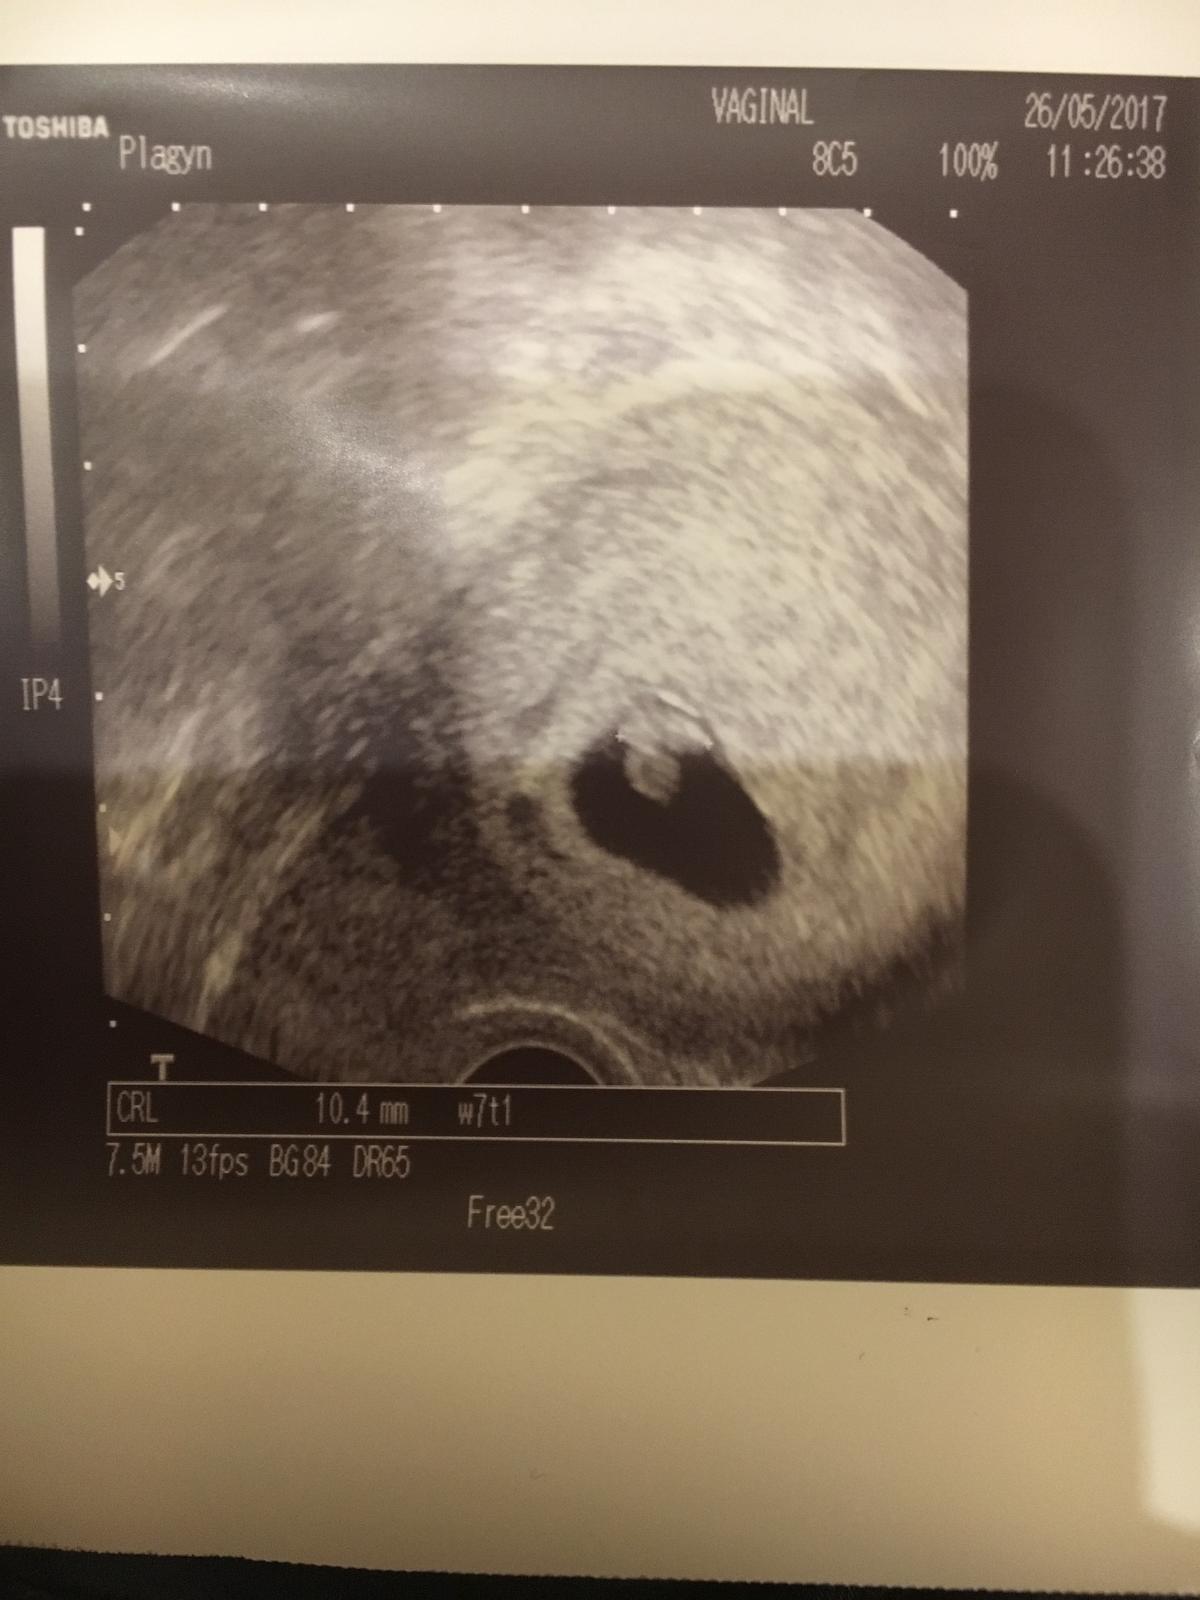

@katmir jako ted v Poho, ale odhadla jsem ho minule spravne, ze se mi to nezdálo.... a jak mi to dneska rekl, ze se toho bal, co tam dneska najde...

Doporučil mi pak skvělou doktorku na prvni screening i dalsi pak kousek od nej a jsou na ni skvele reference co uz jsem cetla pred tim.